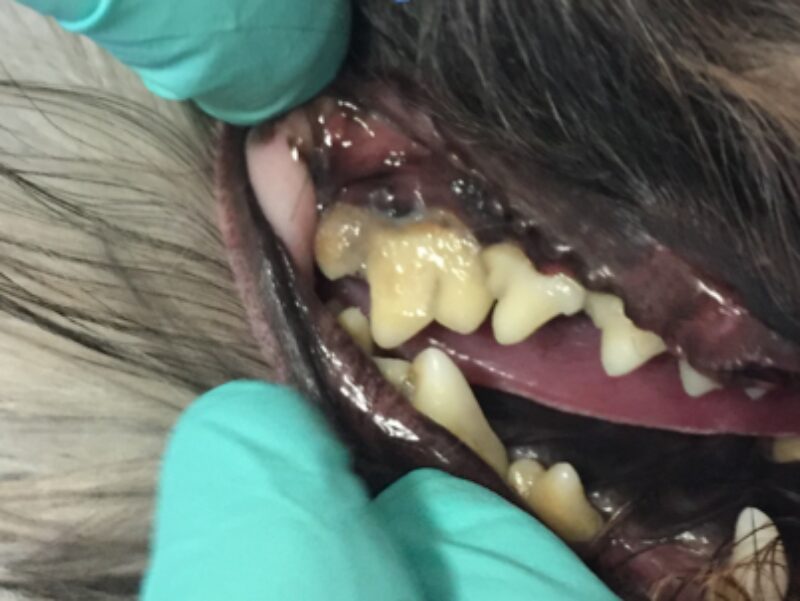

In Narkose sah man auf Leilas Röntgenbildern dann das gesamte Ausmaß ihrer Zahnerkrankung. Bis auf die Canini wiesen alle Zähne hochgradige Wurzelentzündungen mit Osteolysen des Kieferknochens auf. Deshalb konnte man auch schon von außen die Zahnhälse freiliegend sehen. Im Wurzelbereich waren die Veränderungen so schlimm, dass der Unterkiefer kurz vor einer Fraktur stand.

Solche Veränderungen treten oft bei einer hochgradigen Parodontitis auf. Eine Parodontitis ist die Entzündung des gesamten Zahnhalteapparates (also des Kieferknochens, des Zements, der Paradontalfasern und des Zahnfleischs) und wird durch die Bakterien, welche im Plaque enthalten sind, hervorgerufen. Diese zerstören die Anheftung der Gingiva am Zahn, und die Bakterien können bis zur Wurzel vordringen. Hier rufen sie Entzündungsreaktionen des Kieferknochens und der Gingiva hervor, wodurch beide sich zurückziehen und tiefe Paradontaltaschen entstehen lassen. Doch Leila hatte, wie auf den Bildern schön zu sehen ist, kaum Zahnstein oder Plaque.

Natürlich versuchen wir immer so viele Zähne wie möglich zu erhalten. Eine Füllung der betroffenen Zähne, hätte die Entzündung nicht eindämmen können und eine zusätzliche Wurzelspitzenresektion wäre vonnöten gewesen. Da jedoch fast jeder einzelne Zahn betroffen war und der Kiefer sowieso schon sehr wenig Halt besaß, wurde auf eine zusätzliche Traumatisierung durch das Aufbohren des Kiefers verzichtet. Daher war der Erhalt der Zähne in diesem Fall nicht möglich. Hätten wir die Zähne drin gelassen, hätte sich der Kieferknochen nicht erholen können und wäre sicher demnächst gebrochen.